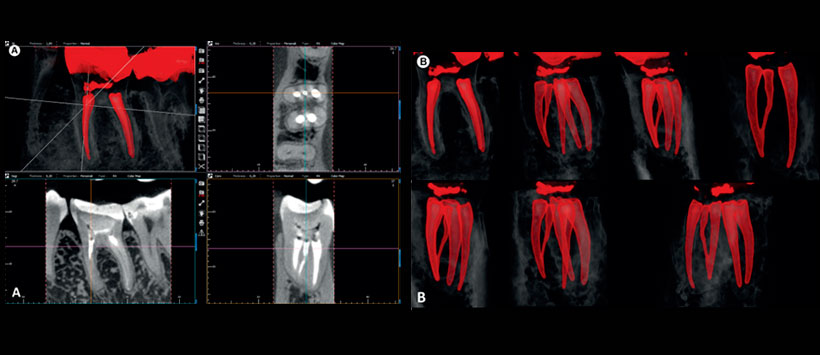

Figura 7: Las imágenes e-Vol DX CBCT (A-C) muestran el canal radicular mesial medio del diente # 36 que se ve fácilmente con un filtro de reconstrucción.